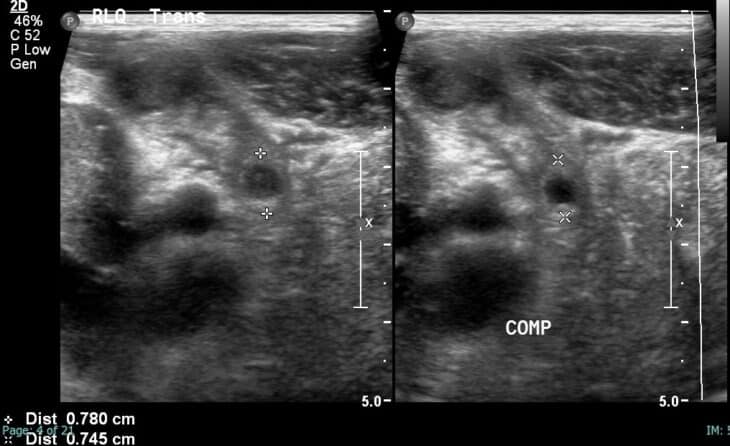

Ultrasound showing distended appendix with surrounding fat stranding ...

Abdominal ultrasound

Ultrasound Imaging of Appendicitis | IntechOpen

Basics techniques needed to evaluate the Appendix! – Integrated ...

Ultrasound in acute appendicitis: why is it so difficult?